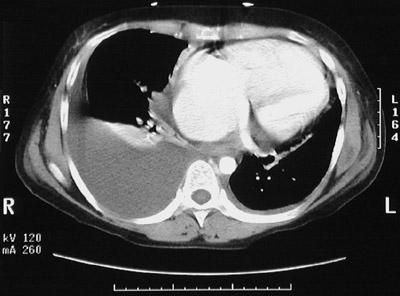

| The chest CT scan here demonstrates a large right pleural effusion. This pleural effusion resulted from right heart failure as a consequence of rheumatic mitral stenosis with chronic pulmonary congestion and subsequent hypertension. Note the enlargement of the right atrium and the right ventricle. Note also that this large effusion has produced atelectasis of the right lower lobe, characterized by a small dense crescent. In the example below, there are smaller bilateral pleural effusions, but the atelectasis is bilateral in lower lobes. |